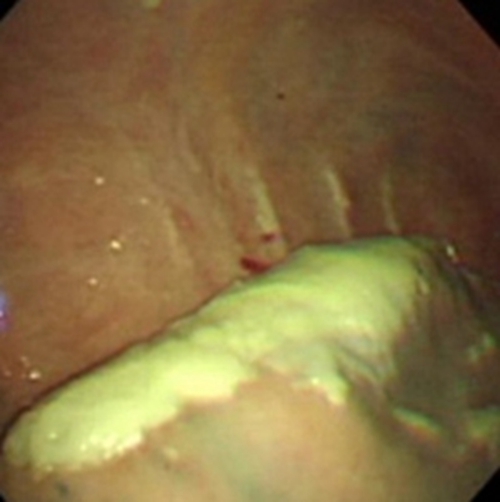

結核性胸膜炎胸腔鏡

結核性胸膜炎胸腔鏡的